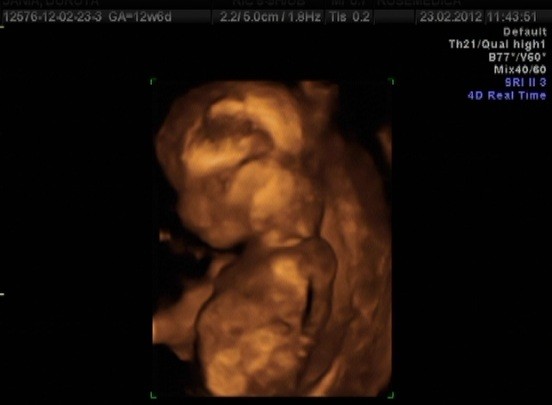

Ja już praktycznie w ryk, ona mówi, że może sprzęt jest już na te wymiary zły, bo ma jakąś tam rozdzielczość i żebym jutro pojechała do szpitala, ale jak zobaczyła, jaka już bliska jestem histerii, zadzwoniła do znajomego lekarza ze szpitala i pojechaliśmy z A od razu. Tam od razu miałam usg genetyczne już przez brzuch i okazało się, że wszystko jest ok :-):-):-) CRL 46 mm -> 11,3 tc

Dziękuję Wam KochaneMoże kiedyś zbiorę się i wytnę kawałek z filmu jak się Dzidzia drapie pogłowie... A to zdjątka (starałam się wybrać jak najlepsze kadry z filmu):

Zobacz załącznik 440449Zobacz załącznik 440450Zobacz załącznik 440451Zobacz załącznik 440452